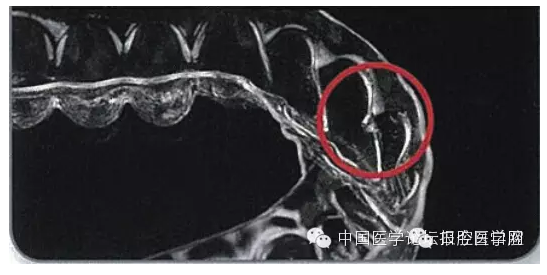

一類是基于石膏模型排牙后,通過(guò)熱壓成型技術(shù)加工矯治器傳統(tǒng)無(wú)托槽隱形矯治技術(shù)。這類技術(shù)也有所差異,一種以Essix系統(tǒng)(圖1)為代表。此技術(shù)是在翻制的石膏模型上移動(dòng)牙齒后設(shè)計(jì)制作單個(gè)矯治器來(lái)矯治輕度的錯(cuò)畸形,其移動(dòng)牙齒的方式是對(duì)擬移動(dòng)的牙齒進(jìn)行修整和緩沖處理,通過(guò)Hilliard熱成型鉗改變矯治器形狀或在牙面上粘接樹脂突給牙齒加力,也可通過(guò)矯治器上的牽引鉤進(jìn)行彈性牽引,逐步實(shí)現(xiàn)牙齒移動(dòng)。

圖1 Essix矯治器加力方式(鉗子加熱,測(cè)量鉗子溫度,使用加熱后的鉗子在矯治器上形成突起,矯治器完成)